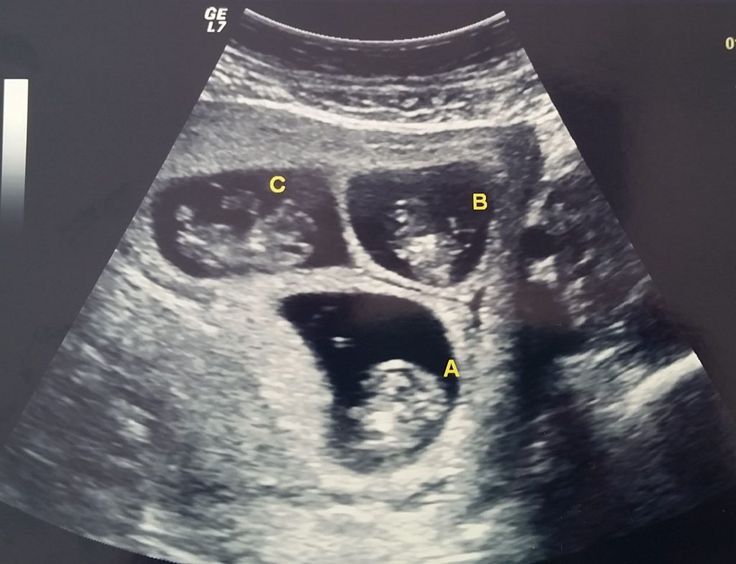

@sacarzs Muito! Ganhei o superpoder de gerar três bebês ao mesmo tempo.